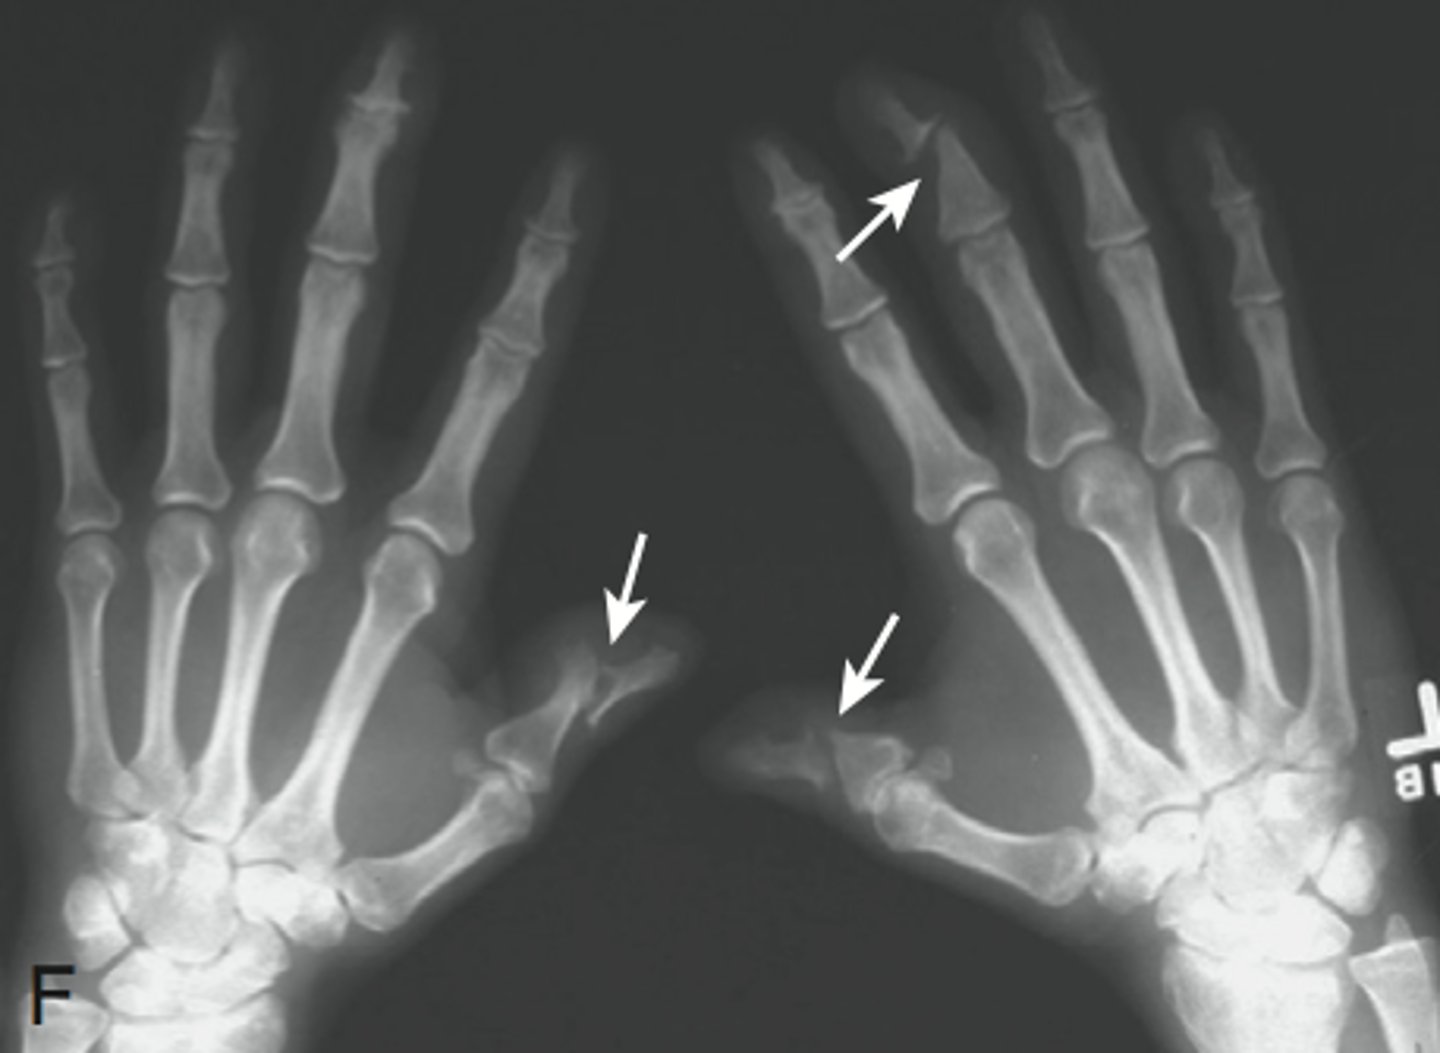

Pencil in cup finding

Most common in psoriatic arthritis (PsA)

Erosion of DIP in pointed manner